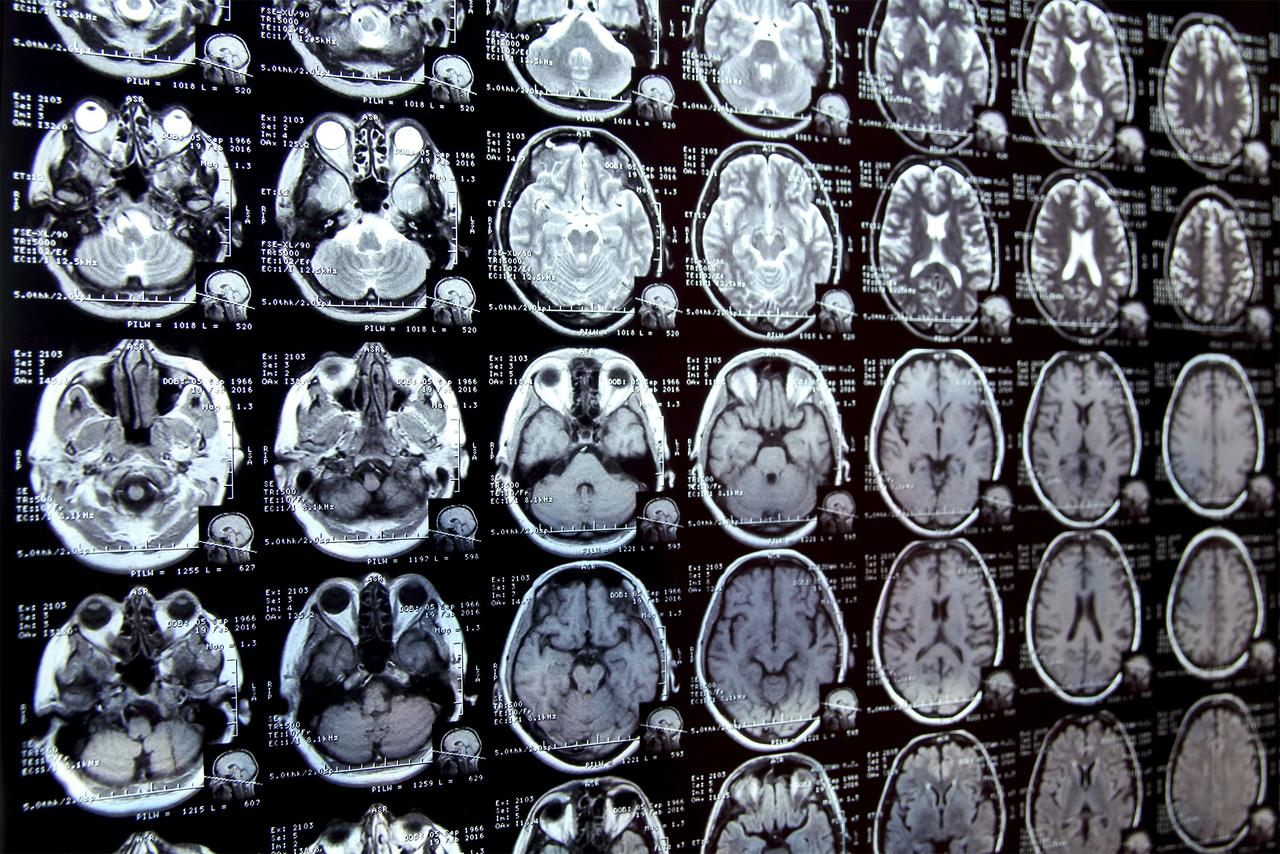

Annotating regions of interest in medical images, a process known as segmentation, is often one of the first steps clinical researchers take when running a new study involving biomedical images. For instance, to determine how the size of the brain's hippocampus changes as patients age, the scientist first outlines each hippocampus in a series of brain scans. For many structures and image types, this is often a manual process that can be extremely time-consuming, especially if the regions being studied are challenging to delineate. To streamline the process, MIT researchers developed an artificial intelligence-based system that enables a researcher to rapidly segment new biomedical imaging datasets by clicking, scribbling, and drawing boxes on the images. This new AI model uses these interactions to predict the segmentation. As the user marks additional images, the number of interactions they need to perform decreases, eventually dropping to zero. The model can then segment each new image accurately without user input. It can do this because the model's architecture has been specially designed to use information from images it has already segmented to make new predictions. Unlike other medical image segmentation models, this system allows the user to segment an entire dataset without repeating their work for each image. In addition, the interactive tool does not require a presegmented image dataset for training, so users don't need machine-learning expertise or extensive computational resources. They can use the system for a new segmentation task without retraining the model. In the long run, this tool could accelerate studies of new treatment methods and reduce the cost of clinical trials and medical research. It could also be used by physicians to improve the efficiency of clinical applications, such as radiation treatment planning. "Many scientists might only have time to segment a few images per day for their research because manual image segmentation is so time-consuming. Our hope is that this system will enable new science by allowing clinical researchers to conduct studies they were prohibited from doing before because of the lack of an efficient tool," says Hallee Wong, an electrical engineering and computer science graduate student and lead author of a paper on this new tool. She is joined on the paper by Jose Javier Gonzalez Ortiz PhD '24; John Guttag, the Dugald C. Jackson Professor of Computer Science and Electrical Engineering; and senior author Adrian Dalca, an assistant professor at Harvard Medical School and MGH, and a research scientist in the MIT Computer Science and Artificial Intelligence Laboratory (CSAIL). The research will be presented at the International Conference on Computer Vision. Streamlining segmentation There are primarily two methods researchers use to segment new sets of medical images. With interactive segmentation, they input an image into an AI system and use an interface to mark areas of interest. The model predicts the segmentation based on those interactions. A tool previously developed by the MIT researchers, ScribblePrompt, allows users to do this, but they must repeat the process for each new image. Another approach is to develop a task-specific AI model to automatically segment the images. This approach requires the user to manually segment hundreds of images to create a dataset, and then train a machine-learning model. That model predicts the segmentation for a new image. But the user must start the complex, machine-learning-based process from scratch for each new task, and there is no way to correct the model if it makes a mistake. This new system, MultiverSeg, combines the best of each approach. It predicts a segmentation for a new image based on user interactions, like scribbles, but also keeps each segmented image in a context set that it refers to later. When the user uploads a new image and marks areas of interest, the model draws on the examples in its context set to make a more accurate prediction, with less user input. The researchers designed the model's architecture to use a context set of any size, so the user doesn't need to have a certain number of images. This gives MultiverSeg the flexibility to be used in a range of applications. "At some point, for many tasks, you shouldn't need to provide any interactions. If you have enough examples in the context set, the model can accurately predict the segmentation on its own," Wong says. The researchers carefully engineered and trained the model on a diverse collection of biomedical imaging data to ensure it had the ability to incrementally improve its predictions based on user input. The user doesn't need to retrain or customize the model for their data. To use MultiverSeg for a new task, one can upload a new medical image and start marking it. When the researchers compared MultiverSeg to state-of-the-art tools for in-context and interactive image segmentation, it outperformed each baseline. Fewer clicks, better results Unlike these other tools, MultiverSeg requires less user input with each image. By the ninth new image, it needed only two clicks from the user to generate a segmentation more accurate than a model designed specifically for the task. For some image types, like X-rays, the user might only need to segment one or two images manually before the model becomes accurate enough to make predictions on its own. The tool's interactivity also enables the user to make corrections to the model's prediction, iterating until it reaches the desired level of accuracy. Compared to the researchers' previous system, MultiverSeg reached 90 percent accuracy with roughly 2/3 the number of scribbles and 3/4 the number of clicks. "With MultiverSeg, users can always provide more interactions to refine the AI predictions. This still dramatically accelerates the process because it is usually faster to correct something that exists than to start from scratch," Wong says. Moving forward, the researchers want to test this tool in real-world situations with clinical collaborators and improve it based on user feedback. They also want to enable MultiverSeg to segment 3D biomedical images. This work is supported, in part, by Quanta Computer, Inc. and the National Institutes of Health, with hardware support from the Massachusetts Life Sciences Center.